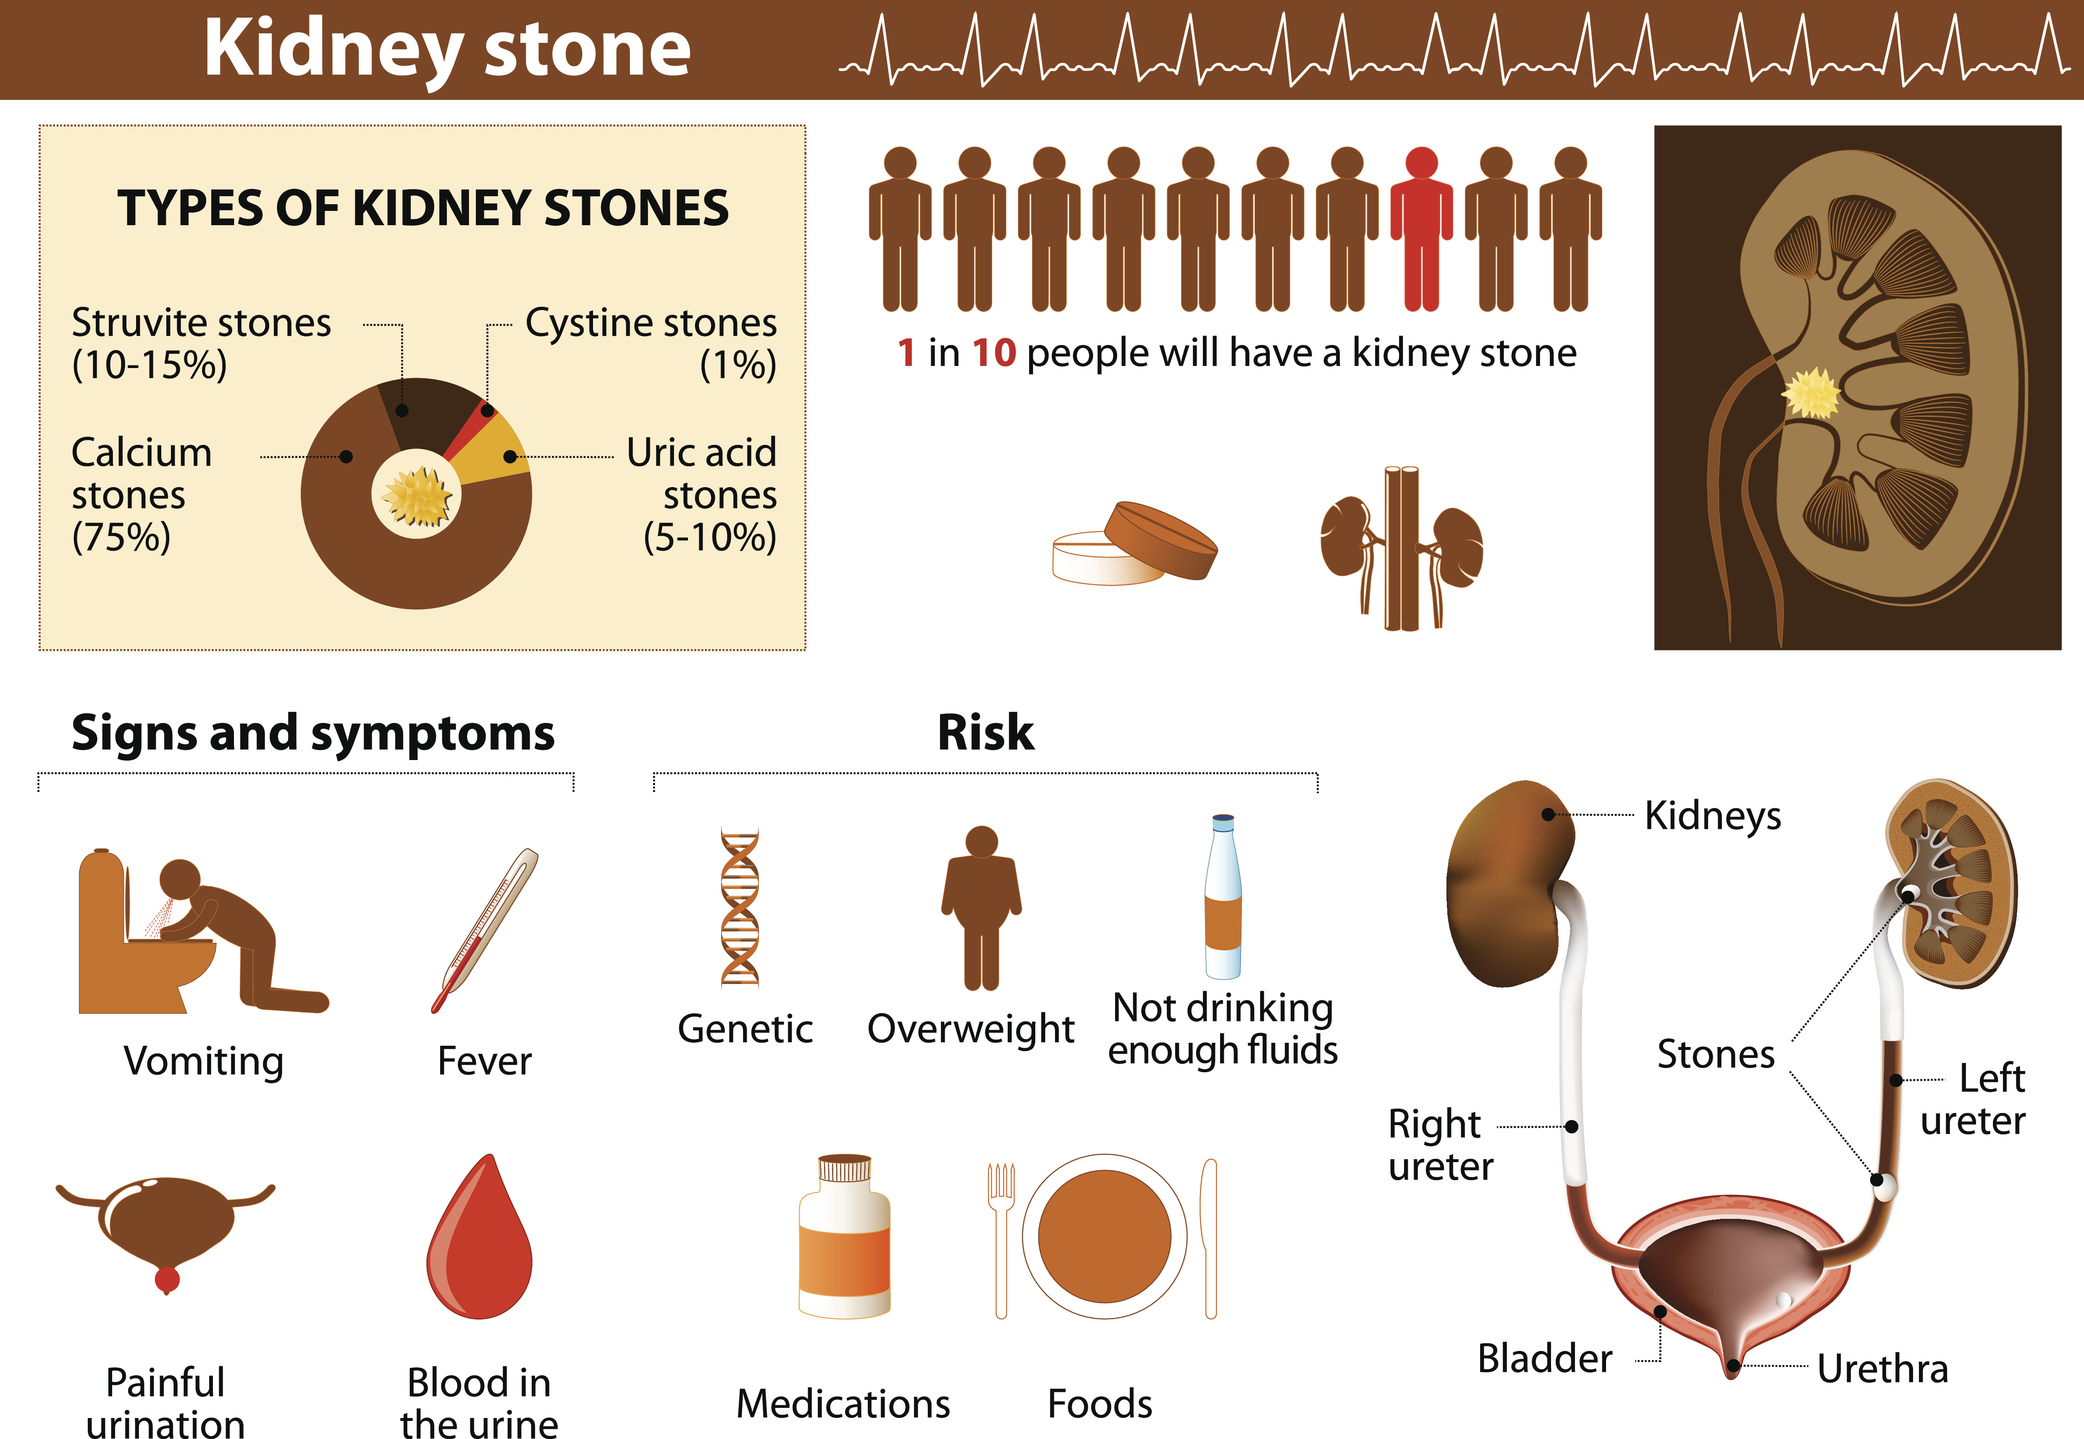

Patients with large kidney stones can benefit from alpha blockers for stone passage. Roughly one in 11 Americans will develop kidney stones in their lifetime. Although kidney stones can be passed while urinating, in some cases, the stones are far too large to pass through, so medical intervention must take place. In some cases, alpha ...click here to read more